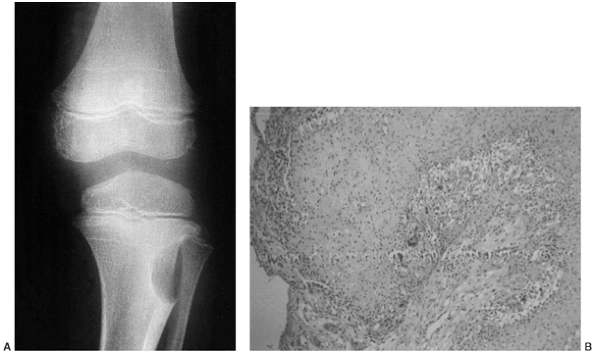

a bone or soft tissue mass includes neoplasia, infection, and trauma.

musculoskeletal tumor can be grave (Fig. 14.1).

Figure 14.1

Anteroposterior radiograph of the knee of a young man who complained of it “giving way.” The orthopaedist who saw the patient suspected a derangement, and the patient eventually had arthroscopic surgery. A radiolucent lesion can easily be seen in the lateral aspect of the proximal tibial metaphysis and epiphysis. This giant cell tumor of bone was missed because the physician did not consider this diagnosis when he was examining the patient or the radiograph. By the time the tumor was recognized, it had grown so large that resection and allograft reconstruction were required. Had it been treated when this radiograph was taken, a curettage and bone graft packing, or polymethyl methacrylate packing, could probably have been done. |